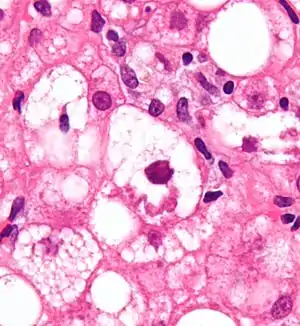

Mallory bodies are highly eosinophilic and thus appear pink on H&E stain. The bodies themselves are made up of intermediate cytokeratin 8/18 filament proteins that have been ubiquitinated, or bound by other proteins such as heat shock proteins, or p62/Sequestosome 1.[5]

Micrograph showing a Mallory body. Original magnification 400X. H&E stain.

Micrograph showing a Mallory body. Original magnification 400X. H&E stain. Micrograph showing a Mallory body. Original magnification 200X. H&E stain.